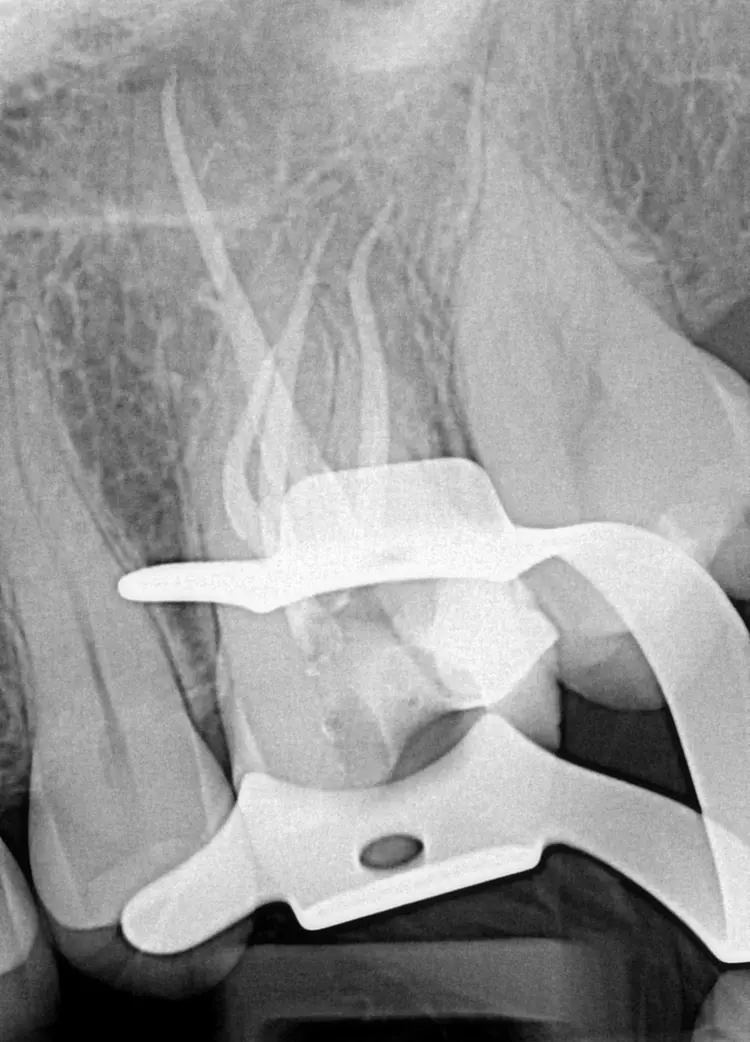

Anschließend erfolgte die mechanische Erweiterung dieses Kanalabschnitts (RECIPROC blue; Abb. 5 „Step 1“). Danach wurde ein manueller Gleitpfad mit K-Feilen der Größe 10 und 15 bis zur Konfluation erstellt, bevor auch dieser Abschnitt bis zur Größe 25 erweitert wurde (RECIPROC blue, Abb. 5 „Step 2“). Die Länge bis zur Konfluation wurde vorab in der DVT-Aufnahme gemessen und nach chemo-mechanischer Desinfektion mit Hilfe eines Guttapercha-Stifts und einer Feile verifiziert.

Die Längen der übrigen Wurzelkanäle wurden elektrometrisch bestimmt und die Kanäle bis zur Größe 25 (mesio-bukkal, disto-bukkal) bzw. 40 (palatinal) erweitert (RECIPROC blue). Nach schallaktivierter chemischer Desinfektion (EDDY, VDW) mit EDTA und NaOCl wurden die Wurzelkanäle getrocknet und thermoplastisch obturiert (Abb. 6 u. 7).